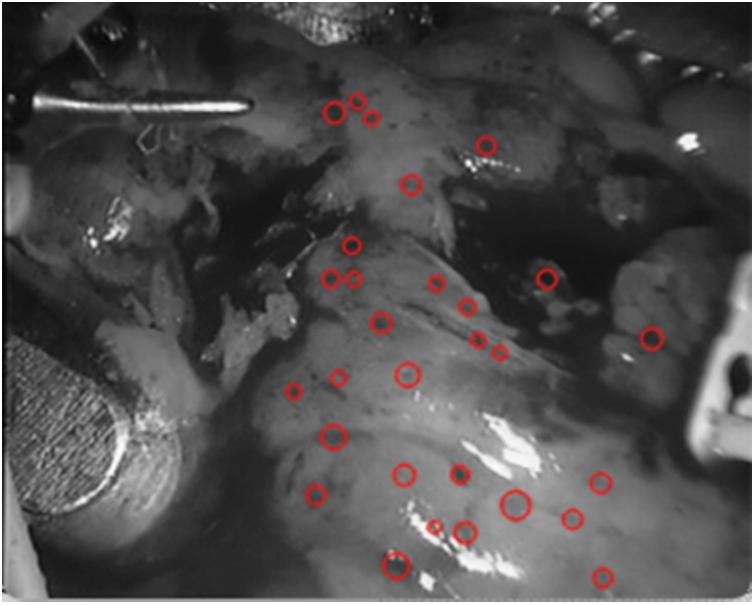

In the subsequent frames, in order to ensure the universality of the test, any frame is selected. In the experiment, any frame selected by the program is

Figure 12: Detection spot map in

As shown in Fig. 12, it can be seen that the spots detected in